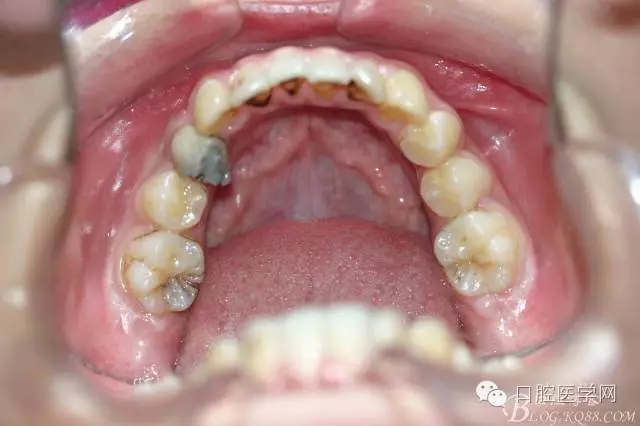

正畸查:替牙合。第一恒磨牙中性合。上牙弓尖圓型下牙弓方圓型。前牙覆合3度覆蓋7.5mm。下前牙咬到上舌側(cè)牙齦。上頜擁擠4.0mm,下頜擁擠

3.0mm。上頜稍前突下頜后縮,上下唇前突,上前牙覆蓋下唇,下唇外翻。面下三分之一過(guò)短,頦唇溝明顯,開(kāi)唇露齒,頦饜窩明顯。顳下頜關(guān)節(jié)開(kāi)閉口無(wú)彈響,無(wú)壓痛,開(kāi)口型開(kāi)口度正常。

正畸前照片: